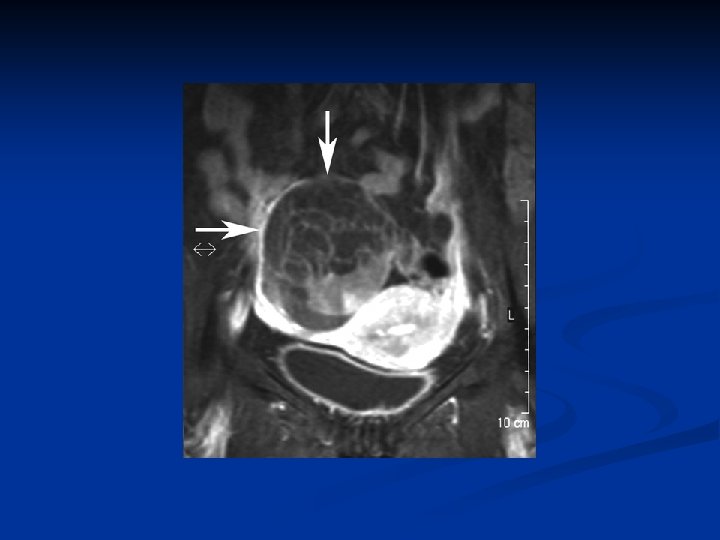

Ovarian Neoplasms-Germ Cell Tumors n Mature Teratomas n Solid n n mature teratomas Usu unilat rare n Mature n n cystic teratomas (dermoid cysts) %95 of all germ cell tumors and %20 of all ovarian tumors Derived from any of the 3 germ cell layers, well differentiated Usually asymptomatic Mostly seen in 20 -40 years of age

Ovarian Neoplasms-Germ Cell Tumors n n n %10 -15 bilateral Rarely bigger than 15 cm Usually unilocular Filled with yellowish coloured fluid with hair, tooth and bones in it There is an irregular solid nodule (Rokitansky nodule) on the inner side of the cyst which consists bones, cartilages and/or fat Complications n n Tortion ( the most)- usually in children and women Rupture ( very rare) Infection Malign transformation ( %1 -2) ( mostly squam. cell carsinoma)

Ovarian Neoplasms-Germ Cell Tumors n n n Diagnosis: TV-USG, MRI Therapy: ovarian cystectomi + examination of the contralateral ovary Immature Teratomas n n n Most common malign germ cell tumors Different from mature cystic teratomas can be seen at all ages, but usu. at reproduc. ages esp first three decades Usu grows quickly outside the capsule and causes adhesions to nearby structures and peritonel cavity implants Usu unilat, AFP may rise 9 -28 cm